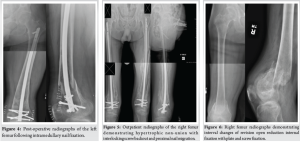

An active, independent 45-year-old male with a history of unresolved T2 paraplegia presented to the emergency department following a motor vehicle accident in which he sustained bilateral closed distal femoral shaft fractures (Fig. 1 and 2) and a left pilon fracture. Surgical intervention was recommended to maintain his current activity levels and to avoid prolonged immobilization. He underwent bilateral femoral retrograde intramedullary nail fixation (Fig. 3 and 4) and left ankle external fixation. The patient was discharged 3 days postoperatively to home with home health assistance; however, he returned the following day due to the inability to perform activities of daily living independently and was ultimately discharged to an acute care rehabilitation facility. He was successfully discharged home from the acute care rehabilitation facility and underwent outpatient removal of the left ankle external fixator and tibiotalocalcaneal (TTC) arthrodesis with a TTC nail 1 month after the initial surgery.

During the patient’s next follow-up visit, 1 month later, the patient complained of palpable hardware around his right knee. Repeat radiographs revealed a hypertrophic non-union with proximal migration of the nail and loosening of the distal interlocking screws (Fig. 5). He was initially treated conservatively; however, symptoms persisted for over 2 months. He then underwent removal of the right distal interlocking screws, augmentation with plate and screw fixation, and revision of the proximal interlocking screws. In a subsequent follow-up 3 weeks later, the patient noted a palpable mass around his left distal thigh. In addition, he developed a sacral decubitus ulcer that required referral to outpatient wound care. Conservative treatment with repeat imaging in 2 months was planned; however, the patient was lost to follow-up. The patient presented to the clinic 1 year later with complaints of palpable distal thigh masses bilaterally and feelings of heaviness in his legs. Radiographs revealed bilateral fracture healing with heterotopic ossification on the left, a well-fixed distal femur plate on the right, and no hardware failure (Fig. 6 and 7). The prominent left-sided heterotopic ossification and palpable right-sided distal femur plate caused significant discomfort. These complications greatly decreased his quality of life and caused him extreme distress. He was referred to a tertiary center for a second opinion, where radiographs revealed bilaterally healed distal femur fractures (Fig. 8 and 9). Removal of the right distal femur plate, left intramedullary nail, and left TTC nail was recommended to improve his quality of life. Unfortunately, the patient passed away from causes indirectly related to his orthopedic injuries before any further follow-up or surgical interventions could take place.